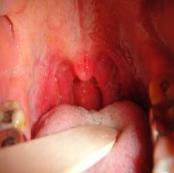

皰疹性咽峽炎

• 皰疹性咽峽炎

628健康網為您分享有關皰疹性咽峽炎的癥狀,皰疹性咽峽炎的治療方法,皰疹性咽峽炎的預防知識,皰疹性咽峽炎的癥狀圖片,皰...